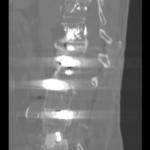

Infiltrațiile transforaminale sunt proceduri medicale minim invazive utilizate pentru diagnosticarea și tratamentul durerilor de spate și a altor afecțiuni legate de coloana vertebrală.

Aceste proceduri implică administrarea de medicamente, cum ar fi corticosteroizii și anestezicele, direct în spațiul în care se află nervii spinali, cunoscut sub numele de foramina.